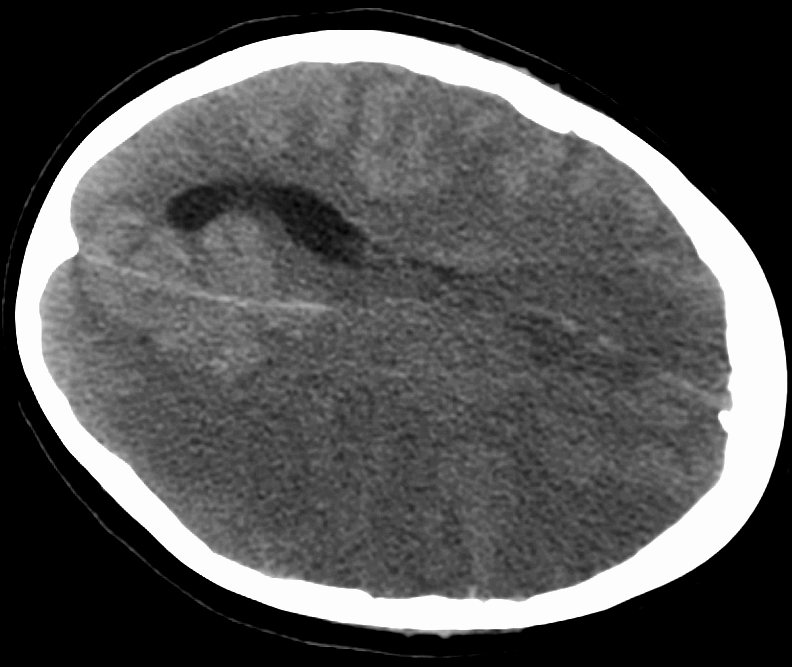

Ишемический инсульт, или инфаркт мозга, — один из самых распространенных типов заболевания, на его долю приходится 87% случаев инсульта. Он является следствием закупорки сосудов и прекращения поступления крови к тому или иному отделу головного мозга. В результате нейроны перестают получать кислород и питательные вещества и погибают. Ишемический инсульт вызывает ухудшение работы отделов мозга, затронутых ишемией, в результате чего развиваются неврологические нарушения, которые могут сохраняться долгое время. Существует высокий риск отложенных постинсультных эффектов, включая снижение когнитивных функций и развитие эмоциональных расстройств (в первую очередь депрессии).

Данные последних лет свидетельствуют, что отдаленные последствия инсульта могут быть связаны не только с повреждениями ишемизированной зоны мозга, но и вторичными повреждениями гиппокампа — структуры, контролирующей как обучение и память, так и эмоции.

Гиппокамп особенно чувствителен к избытку в организме стрессорных глюкокортикоидных гормонов, и именно они входят в число факторов риска тяжелого исхода инсультов и развития когнитивных нарушений.Обычно в доклинических исследованиях используют специальные модели ишемического инсульта на грызунах. Тем не менее, большинство препаратов, показавших хорошие результаты, при использовании в терапии оказались неэффективны. Авторы проекта предположили, что это может быть связано с тем, что не учитываются эффекты стресс-реакции организма, которая проявляется в виде накопления гормона стресса (кортизола у человека и кортикостерона у грызунов). Вместе с тем она имеет огромное значение в возникновении, течении и исходе ишемического инсульта.

Российские ученые из Института высшей нервной деятельности и нейрофизиологии РАН (Москва) и Научно-практического психоневрологического центра имени З. П. Соловьева (Москва) провели сравнительное исследование двух популярных моделей закупорки среднемозговой артерии у грызунов с использованием экспериментальных методов Коидзуми и Лонга на 85 самцах крыс. Спустя три дня степень ишемического повреждения, смертность, неврологический дефицит и потеря веса животных в этих моделях были одинаковыми. Однако у грызунов модели метода Коидзуми наблюдалось нарушение функции коры надпочечников, что привело к повышенному уровню гормона стресса в крови и его накоплению в гиппокампе. У этих животных наблюдали также увеличение количества провоспалительных цитокинов (веществ, способствующих воспалению) в этом отделе мозга, что может способствовать его повреждению и отсроченным нарушениям поведения.